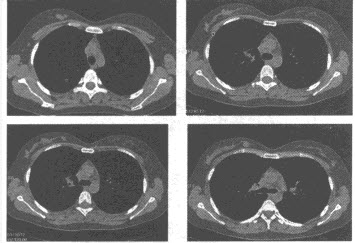

(多选题)关于该病转移方式描述不正确的是()

A:经淋巴结转移首先可分别转移到幽门上组、下组、胃上组或脾胰组

B:可通过胸导管转移到肺门淋巴结或左锁骨上淋巴结

C:通过门静脉转移到肝内十分常见

D:肺、骨转移较常见

E:晚期可种植于腹膜、卵巢或直肠陷凹上